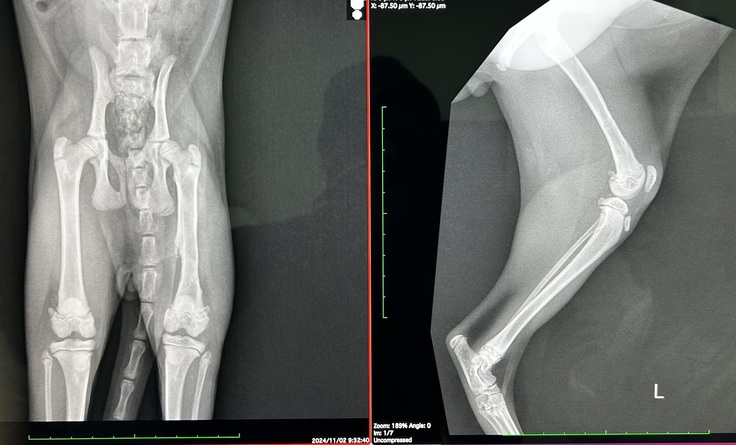

11月2日 〜 治療経過報告③ 〜

本日は9/26の抜糸以来の手術病院での診察です。

約1ヶ月のリハビリ結果とカクカク歩きの原因や対処について相談する予定で行きました。

本日の診察では、良くなっている部分と懸念が残る部分があり、それぞれ先生からご意見をいただきました。

【良くなっている部分】

◯ 左脚が使える状態になっている。

→ 骨折の影響で左脚を引きずっていましたが、リハビリを続けた結果、現在では左脚を使えるようになりました。

◯ 神経反応は確認

→ 脚気反応や脚先の神経反応が確認され、神経麻痺などの懸念はなくなりました。

【懸念が残る部分】

◯ カクカク歩行

→骨折で脚を使えない影響で、筋肉が硬くなり曲げ伸ばししきれない。

→大腿神経の影響で、体重をかけられない可能性があること。

先生は「これをすれば確実に良くなる」という明確な方法は現段階では言い切れないと正直に話してくださいました。ただ、ごろうは生後4ヶ月の成長期の子なので、改善の可能性を信じてできることを試していくことが大切だとアドバイスを受けました。これが将来のごろうにとって良い結果につながるかもしれません。